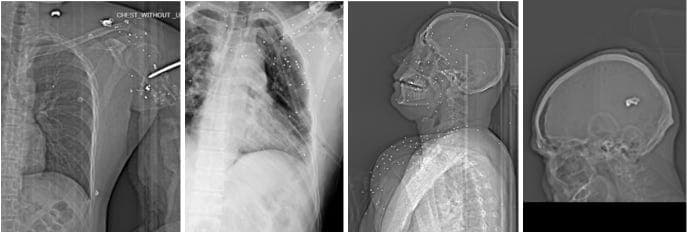

1. Head, face, eyes, and neck

A significant number of injuries involved the face and eye sockets, often with multiple shotgun pellets embedded around the orbit. Doctors repeatedly warned of a high risk of permanent blindness.

In some cases, pellets were lodged near the skull base or even inside the cranial cavity, raising the risk of brain injury, permanent neurological damage, or death.

One case showed a bullet in the neck causing tracheal displacement, with signs consistent with bleeding and swelling. Physicians noted the potential for major vascular injury, stroke, or fatal hemorrhage.

2. Chest and lungs

Several patients suffered penetrating chest trauma. Recurrent findings included:

- Pneumothorax (air compressing the lung)

- Hemothorax (blood filling the chest cavity)

- Subcutaneous air from open wounds

- Chest tubes inserted as emergency intervention

Untreated, such injuries can be fatal within minutes. Some scans suggested projectiles may have traversed the chest, potentially damaging multiple organs.

B) 7.62×39mm high-velocity bullets

10 cases

These injuries were consistent with ammunition fired from Kalashnikov-pattern assault rifles such as the AK-47 and its variants (including AKM, Type 56, and locally produced derivatives).

Radiological features included:

- Large deformed metal projectiles

- Deep penetration

- Severe bone fragmentation

- Projectiles lodged inside the body

- Chest trauma with pneumothorax

- One case of brain injury with high mortality risk

- One case of a neck wound with tracheal displacement